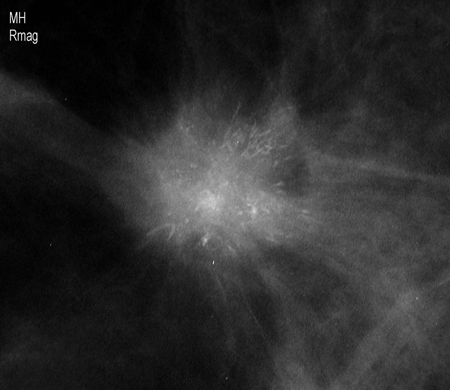

Imagen aumentada en la que se observa una masa espiculada irregular con calcificaciones asociadas

Cortesía de la Dra. Nancy Pile, University of Louisville; utilizada con autorización